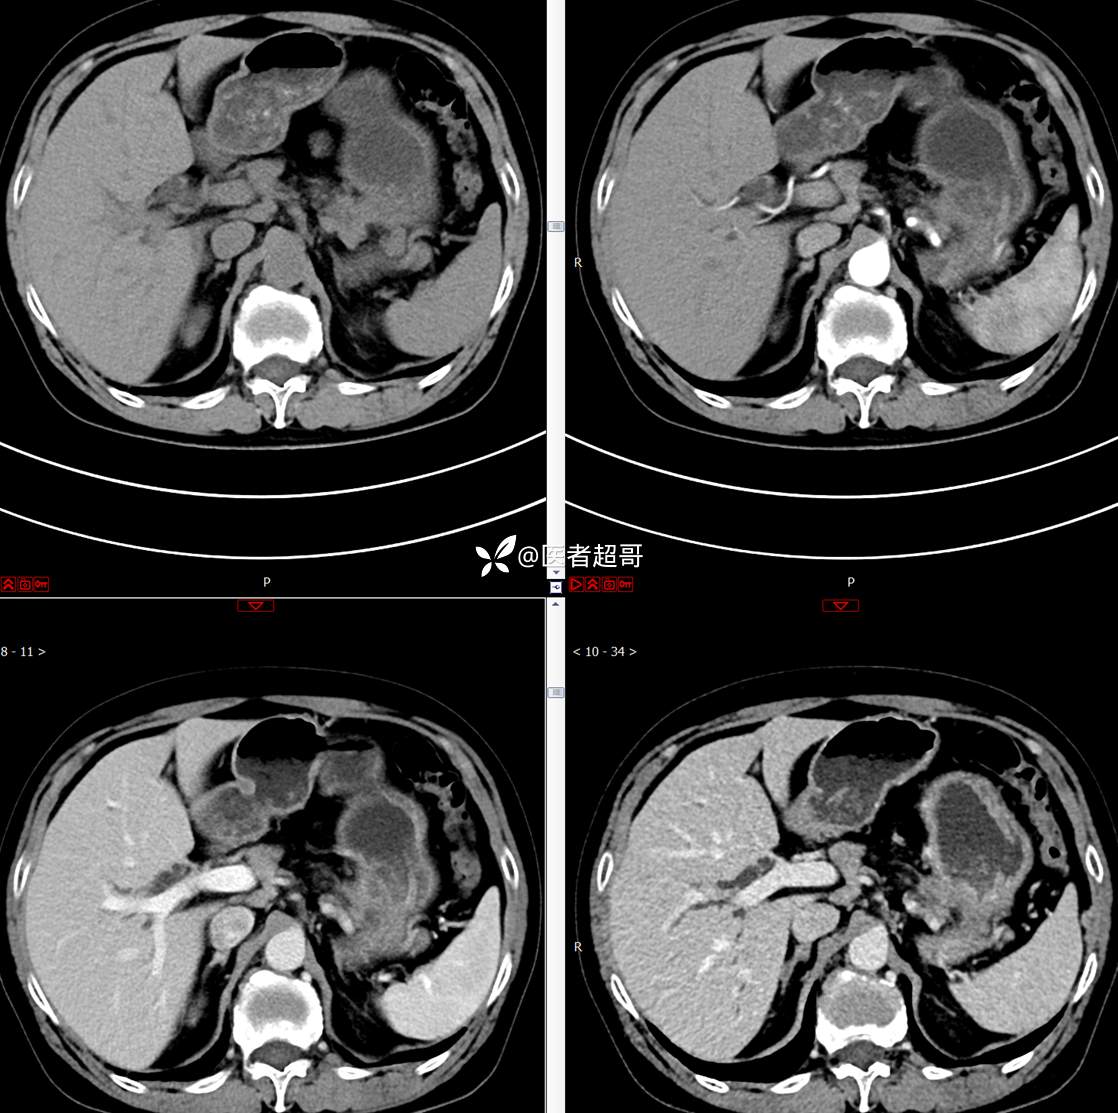

【影诊笔记772】腹痛就诊,发现肾脏病变,CT、MRI齐全,请高诊!

主 诉:间断腹痛15天

现病史:患者15天前无明显原因及诱因出现腹部疼痛不适,呈间断性钝痛,右下腹为著,无尿频、尿急、尿不尽,无发热、寒战,无腹胀。于市中心卫生院住院治疗,超声示:胰头低回声包块,胆系扩张,左肾囊肿,胆囊壁毛糙,胆囊内胆汁淤积。患者为求进一步诊治,遂以“肾盂肿瘤”收入院,患者自发病以来,神志清,精神可,饮食睡眠可,大便无明显异常,近期体重无明显增减。